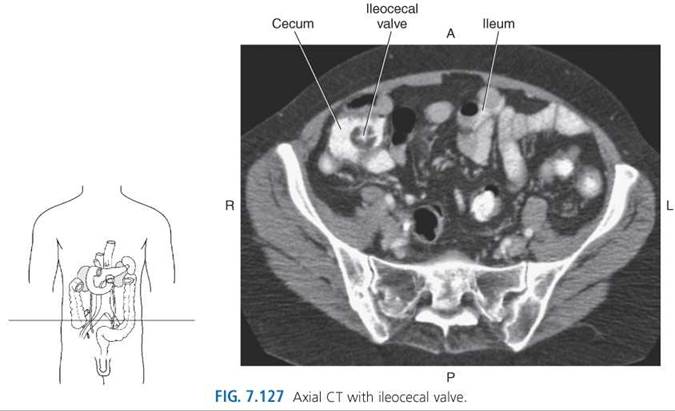

The small intestine (small bowel) is located between the pylorus and ileocecal valve and consists of loops of bowel averaging 6 to 7 meters in length. It can be subdivided into the duodenum, jejunum, and the ileum (Figs. 7.120 and 7.121). The proximal portion of the small intestine is the duodenum, which begins at the gastric pylorus and curves around the head of the pancreas, forming the letter C (Figs. 7.118-7.122). The duodenum is mostly retroperitoneal, making it less mobile than the rest of the small intestine. Although quite short, the duodenum is divided into four portions. The first (superior) portion, located in the anterior pararenal space, is formed by the first 2 inches of the duodenum, the conical-shaped duodenal bulb. It is suspended in the abdomen by the hepatoduodenal ligament and is the most common site for peptic ulcer formation. The second (descending) portion is formed by the next 4 inches of the duodenum that descends along the right side of the vertebral column just anterior to the right renal hilum; it contains the ampulla of Vater and receives pancreatic and biliary drainage. The third (horizontal) portion is about 10 cm long and runs horizontally in front of the third lumbar vertebra. In its horizontal course from right to left, the third portion of the duodenum runs anterior to the IVC, aorta, and inferior mesenteric artery, and posterior to the superior mesenteric artery (Figs. 7.123 and 7.124). The fourth (ascending) portion is about 2.5 cm in length and ascends on the left side of the aorta to the level of the L2 vertebra, where it meets up with the jejunum at the duodenojejunal flexure. The duodenojejunal flexure is fixed in place by the ligament of Treitz, a suspensory ligament created from the connective tissue located around the celiac trunk and left crus of the diaphragm (Fig. 7.122). This location marks the entry of the small bowel into the peritoneal cavity. The remainder of the small intestine, the jejunum and ileum, is suspended from the posterior abdominal wall by a fan-shaped mesentery. The jejunum is approximately 2.5 m long (about 40% of the small bowel) and occupies the left upper abdomen or umbilical region of the abdomen (Figs. 7.120-7.124). This section of small bowel is where the bulk of chemical digestion and nutrient absorption occurs. The jejunum contains numerous circular folds that give it a feathery appearance on diagnostic imaging examinations. It also has a thicker and more vascular wall than the ileum. The ileum is the longest portion of the small intestine, averaging 3.5 m in length (about 60% of the small bowel), and is located in the right lower abdomen (Figs. 7.120, 7.121, and 7.124-7.126). It is in the ileum that intrinsic factor from the stomach combines with vitamin B12 for absorption in the terminal ileum. Vitamin B12 is essential for normal red blood cell formation and nervous system function. The loops of ileum terminate at the ileocecal valve, a sphincter that controls the flow of material from the ileum into the cecum of the large intestine (Figs. 7.120, 7.121, and 7.127). The segments of the small intestine receive blood entirely from branches of the superior mesenteric artery and are drained by branches of the superior mesenteric vein.